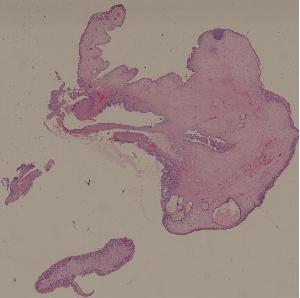

23. Inflammatory polyp